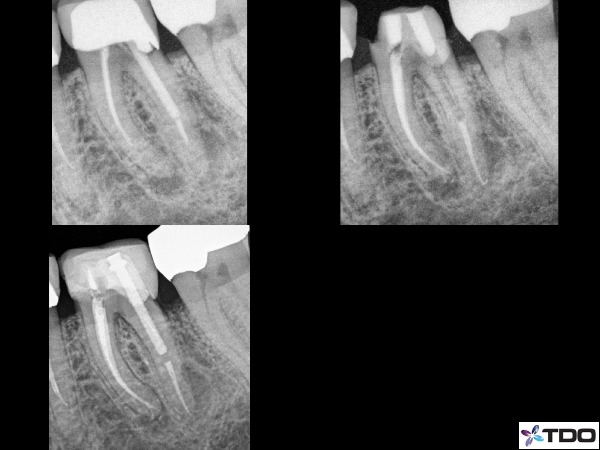

The third significant advantage is that if the restorative dentist wishes to keep this material in place they can simply just fill the access with their material of choice and proceed to prepare the pre-endodontic build-up in the crown prep process. Often times we will roughly prep the build-up ourselves before referring the patient back to the dental office (figure 2).

Fig. 2: The upper left x-ray is the presenting condition of the tooth. There was recurrent decay at the distal margin, thus I removed the crown to remove the decay and retreat the tooth. I rebuilt the tooth with composite and then reaccessed with 3 separate access points occlusal. This allowed for more bulk of build-up material. You can see the temporary material in the separate access points for each canal. I also roughly prep’d the tooth for crown work. The lower left x-ray shows the condition with a post and a temporary crown in place. In this case the pre-endodontic build-up was used as the final build-up for the crown.